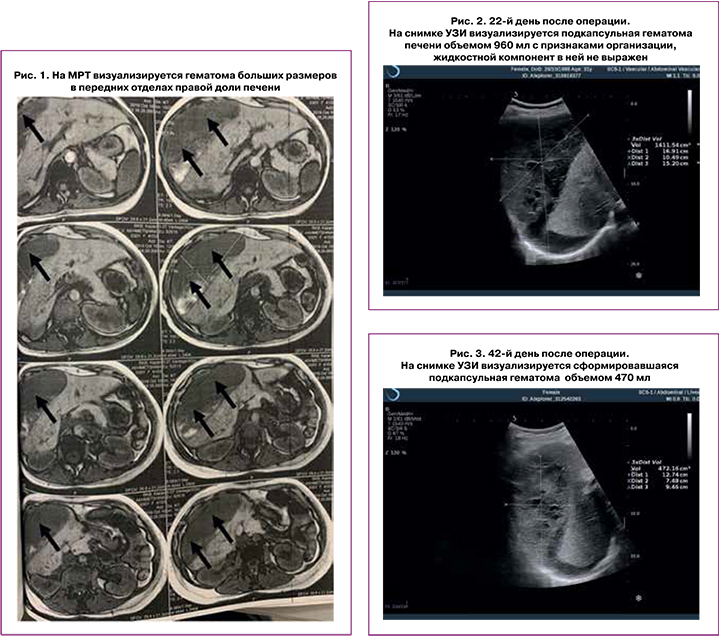

Первобеременная А., 30 лет, индекс массы тела 23,5 кг/м2, наблюдалась в женской консультации с раннего срока. До беременности отмечала эпизоды повышения артериального давления до 150/90 мм рт. ст., самостоятельно и нерегулярно принимала гипотензивные препараты. До 35 недель беременности артериальное давление не превышало 120/80 мм рт. ст. В течении одной недели появляются отеки нижних конечностей, артериальное давление повышается до 140/90–150/90 мм рт. ст. на фоне антигипертензивной терапии (метилдопа). Анализ мочи на суточную протеинурию отрицательный. На сроке 36 недель 6 дней остро возникли боли в эпигастральной области и диспептические расстройства – тошнота и рвота. Экстренно госпитализирована, проведена консультация хирурга для исключения острой хирургической патологии. При лабораторном обследовании наблюдалось относительное прогрессирование тромбоцитопении (со 180 до 160×109/л), повышение уровня трансаминаз (АЛТ 981 Ед/л, АСТ 1200 Ед/л, ЛДГ 1195 Ед/л), коагулограмма в пределах нормы. На этапе подготовки к родоразрешению проводится медикаментозная терапия: раствор сульфата магния 6 мл/ч, эгилок 25 мг 2 р/д, раствор альбумина 100,0 в/в кап., эниксум 0,3 п/к 1р/д. Однако, в этот же день в связи с тяжелой преэклампсией и HELLP-синдромом на сроке 37 недель была родоразрешена путем операции кесарева сечения. Операция была выполнена лапаротомией по Пфанненштилю, поперечным разрезом матки в нижнем сегменте, без технических сложностей. Был извлечен плод мужского пола массой 3440 г, рост 50 см, оценка по шкале Апгар 7–8 баллов. Кровопотеря по данным гравиметрического учета составила 610 мл. Однако, через два часа после операции были отмечены клинические признаки постгеморрагической анемии и снижение гемоглобина в периферической крови с исходного до операции 110 г/л до 87 г/л. Коагулограмма – АЧТВ 34 сек, ПТИ 70%, МНО 1,2, фибриноген 4,24 г/л, протромбин 17,0 сек. Наружного кровотечения не отмечено. По данным УЗИ свободной жидкости в брюшной полости не выявлено. Правая доля печени имеет размеры 142×102×65 мм, левая – 82×122×63 мм. На передней поверхности правой доли печени субкапсульно было обнаружено жидкостное образование с негомогенным содержимым размерами 144×59 мм, объемом 380 мл. С целью уточнения диагноза проведено РКТ с введением контраста. По ее результатам печень увеличена краниокаудально до 201 мм, структура паренхимы неоднородная за счет множественных и неравномерных скоплений контраста, в передних отделах правой доли субкапсулярно определяется неоднородная гематома размерами 166×69×146 мм. По данным МРТ (рис. 1) также подтверждено наличие подкапсульной гематомы верхних, передних и наружных отделов правой доли печени линзовидной формы, размерами 165×65×140 мм, неоднородной структуры с Т1-гипер- и Т2-гипоинтенсивными сгустками и жидкостным компонентом (лизированной кровью).

При последующем ультразвуковом контроле, выполненном на 22-й день после операции (рис. 2), были отмечены признаки организации подкапсульной гематомы правой доли печени, а также эхографические признаки начальной реканализации яичниковой вены и внутренней подвздошной вены справа.

При ультразвуковом исследовании органов брюшной полости, выполненном на 42-й день после операции (рис. 3), визуализировалась под диафрагмой и латерально от правой доли и верхней трети правого бокового кармана гематома объемом до 470 мл. В толще гематомы сосудов нет.